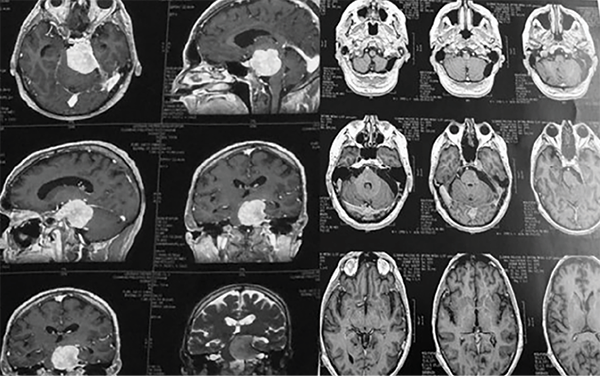

Uno de los abordajes más versátiles para la extirpación de meningiomas petroclivales que no se extienden hacia la fosa media es el abordaje retrosigmoideo (Figuras 6 y 7). El abordaje retrosigmoideo es más simple y fácil de realizar en comparación con los abordajes mencionados anteriormente. Está indicado cuando el tumor se encuentra principalmente en la fosa posterior, con una pequeña extensión en la fosa media y la porción posterior del seno cavernoso. En decúbito lateral o dorsal con rotación y extensión lateral de la cabeza, la incisión de la piel comienza en la región retromastoidea, 5 centímetros detrás del conducto auditivo externo, y se extiende 2 centímetros desde la punta de la mastoides, terminando en la parte superior del cuello. La fascia y los músculos se cortan hacia abajo, exponiendo el hueso occipital, el asterion y la región retromastoidea. Se realiza una craneotomía de cuatro centímetros de diámetro exponiendo los senos transverso y sigmoideo. La vena emisaria del mastoideo se coagula y se corta. Se hace una incisión en la duramadre paralelamente al seno sigmoideo, retrayendo ligeramente el aspecto lateral del cerebelo. El primer paso después de abrir la duramadre es drenar el líquido cefalorraquídeo de la cisterna cerebelomedular. Los pares craneales VII y VIII generalmente se encuentran posteriores a la cápsula tumoral, a menudo se incorporan al tumor, y se debe realizar una disección muy cuidadosa con monitoreo neurofisiológico intraoperatorio. El V par craneal se encuentra en el polo superior del tumor o se desplaza hacia arriba con el IV par craneal a través del margen libre del tentorio. El VI par craneal generalmente se encuentra en la parte anterior y en la superficie medial del tumor. Su identificación y disección solo es posible después de una extensa reducción de la lesión. Después de la coagulación de los accesorios durales, se realiza una resección intracapsular fragmentada entre los nervios craneales, a través de "ventanas" (tentorio-V; V-VII y VIII; VII y VIII-IX, X, XI). El envolvimiento tumoral de la arteria basilar y sus ramas, así como la arteria vertebral, es común en los exámenes preoperatorios. Sin embargo, generalmente hay un buen plan de disección durante la cirugía (Figura 5). La disección del plano aracnoideo alrededor de los vasos y nervios craneales es necesaria para preservar estas estructuras. El abordaje retrosigmoideo permite la resección del tumor desde el foramen yugular hasta la parte posterior del seno cavernoso. El tumor con extensión a la fosa media puede resecarse, abriendo el tentorio y drenando el tubérculo suprameatal y el ápex petroso14. Después de la extirpación total del tumor, se debe realizar un cierre preciso de la duramadre. Todas las celdas mastoideas abiertas son selladas con injerto muscular y pegamento de fibrina. Algunos modelos fueron desarrollados para tratar de medir varios elementos de la resecabilidad de los meningiomas petroclivales. Entre ellos, Abdel-Aziz et al desarrollaron un mecanismo para predecir la reexpansión posquirúrgica del tronco encefálico después de los abordajes petrosos anteriores o posteriores. Se propuso una nueva escala de clasificación basada en el tamaño de la resección y la calidad de la descompresión del tronco encefálico. Para Siwanuwatn et al el abordaje transcoclear es el que proporciona el espacio más amplio para el acceso petroclival; sin embargo, se debe sacrificar la audición.15 Todos estos abordajes son complejos y con un gran potencial de complicaciones si no hay un conocimiento claro de la anatomía. Los autores sugieren capacitación en un laboratorio de microcirugía y anatomía antes de llevar a cabo estos abordajes.

Figura 6: Meningioma petroclival del clivus superior y medio sin extensión de la fosa media. (A) Se seleccionó el abordaje retrosigmoideo para este caso, con el paciente posicionado en decúbito lateral (Park Bench) (2). La craneotomía o craniectomía con reconstrucción con cemento óseo se debe realizar exponiendo parte del seno sigmoideo y transversal. Con eso, la apertura de la duramadre.

Figura 7: Meningioma petroclival grande resecado por abordaje suboccipital. Se observa un pequeño componente tumoral que se extiende en la fosa media en continuidad con el tentorio. Esta parte tumoral se resecó abriendo el tentorio a través de la fosa posterior. No se resecó una pequeña extensión en el seno cavernoso.